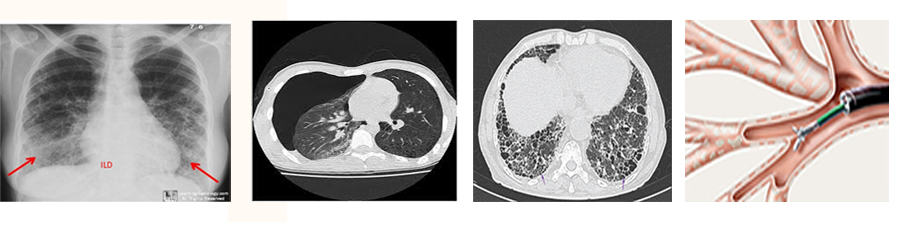

• Chest X-ray showing reticulo-nodular opacity

• HRCT chest showing ground glass opacity

• HRCT Chest showing honeycombing